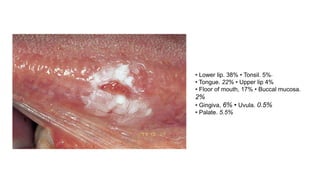

โ€ข Lower lip. 38% โ€ข Tonsil. 5%~

โ€ข Tongue. 22% โ€ข Upper lip 4%

โ€ข Floor of mouth, 17% โ€ข Buccal mucosa.

2%

โ€ข Gingiva, 6% โ€ข Uvula. 0.5%

โ€ข Palate. 5.5%